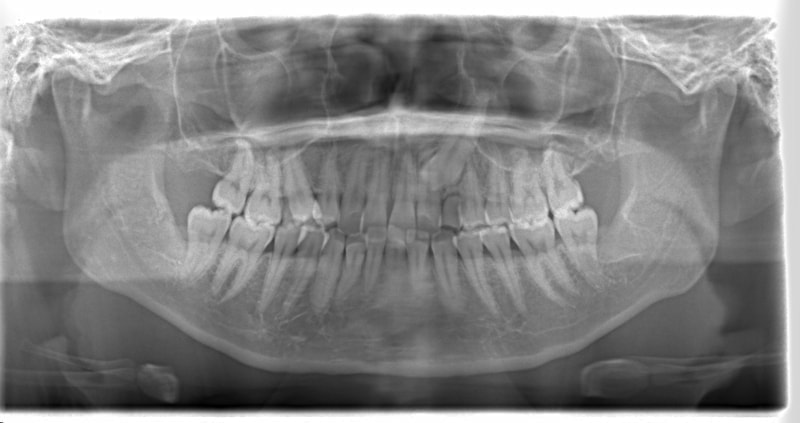

症例紹介

左上3番埋伏歯

治療法:フルパッシブブラケット:T21

治療開始時